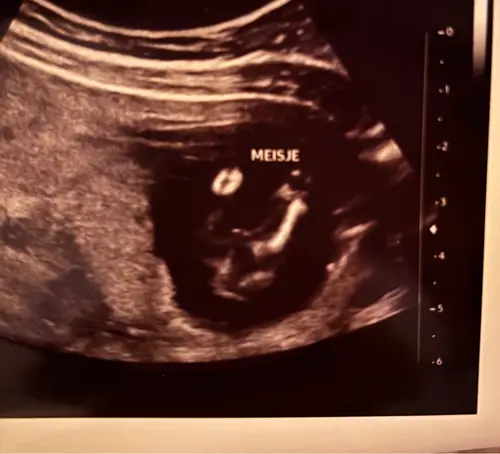

Is dit duidelijke een meisje? Door de nub dachten we namelijk eerst een jongen